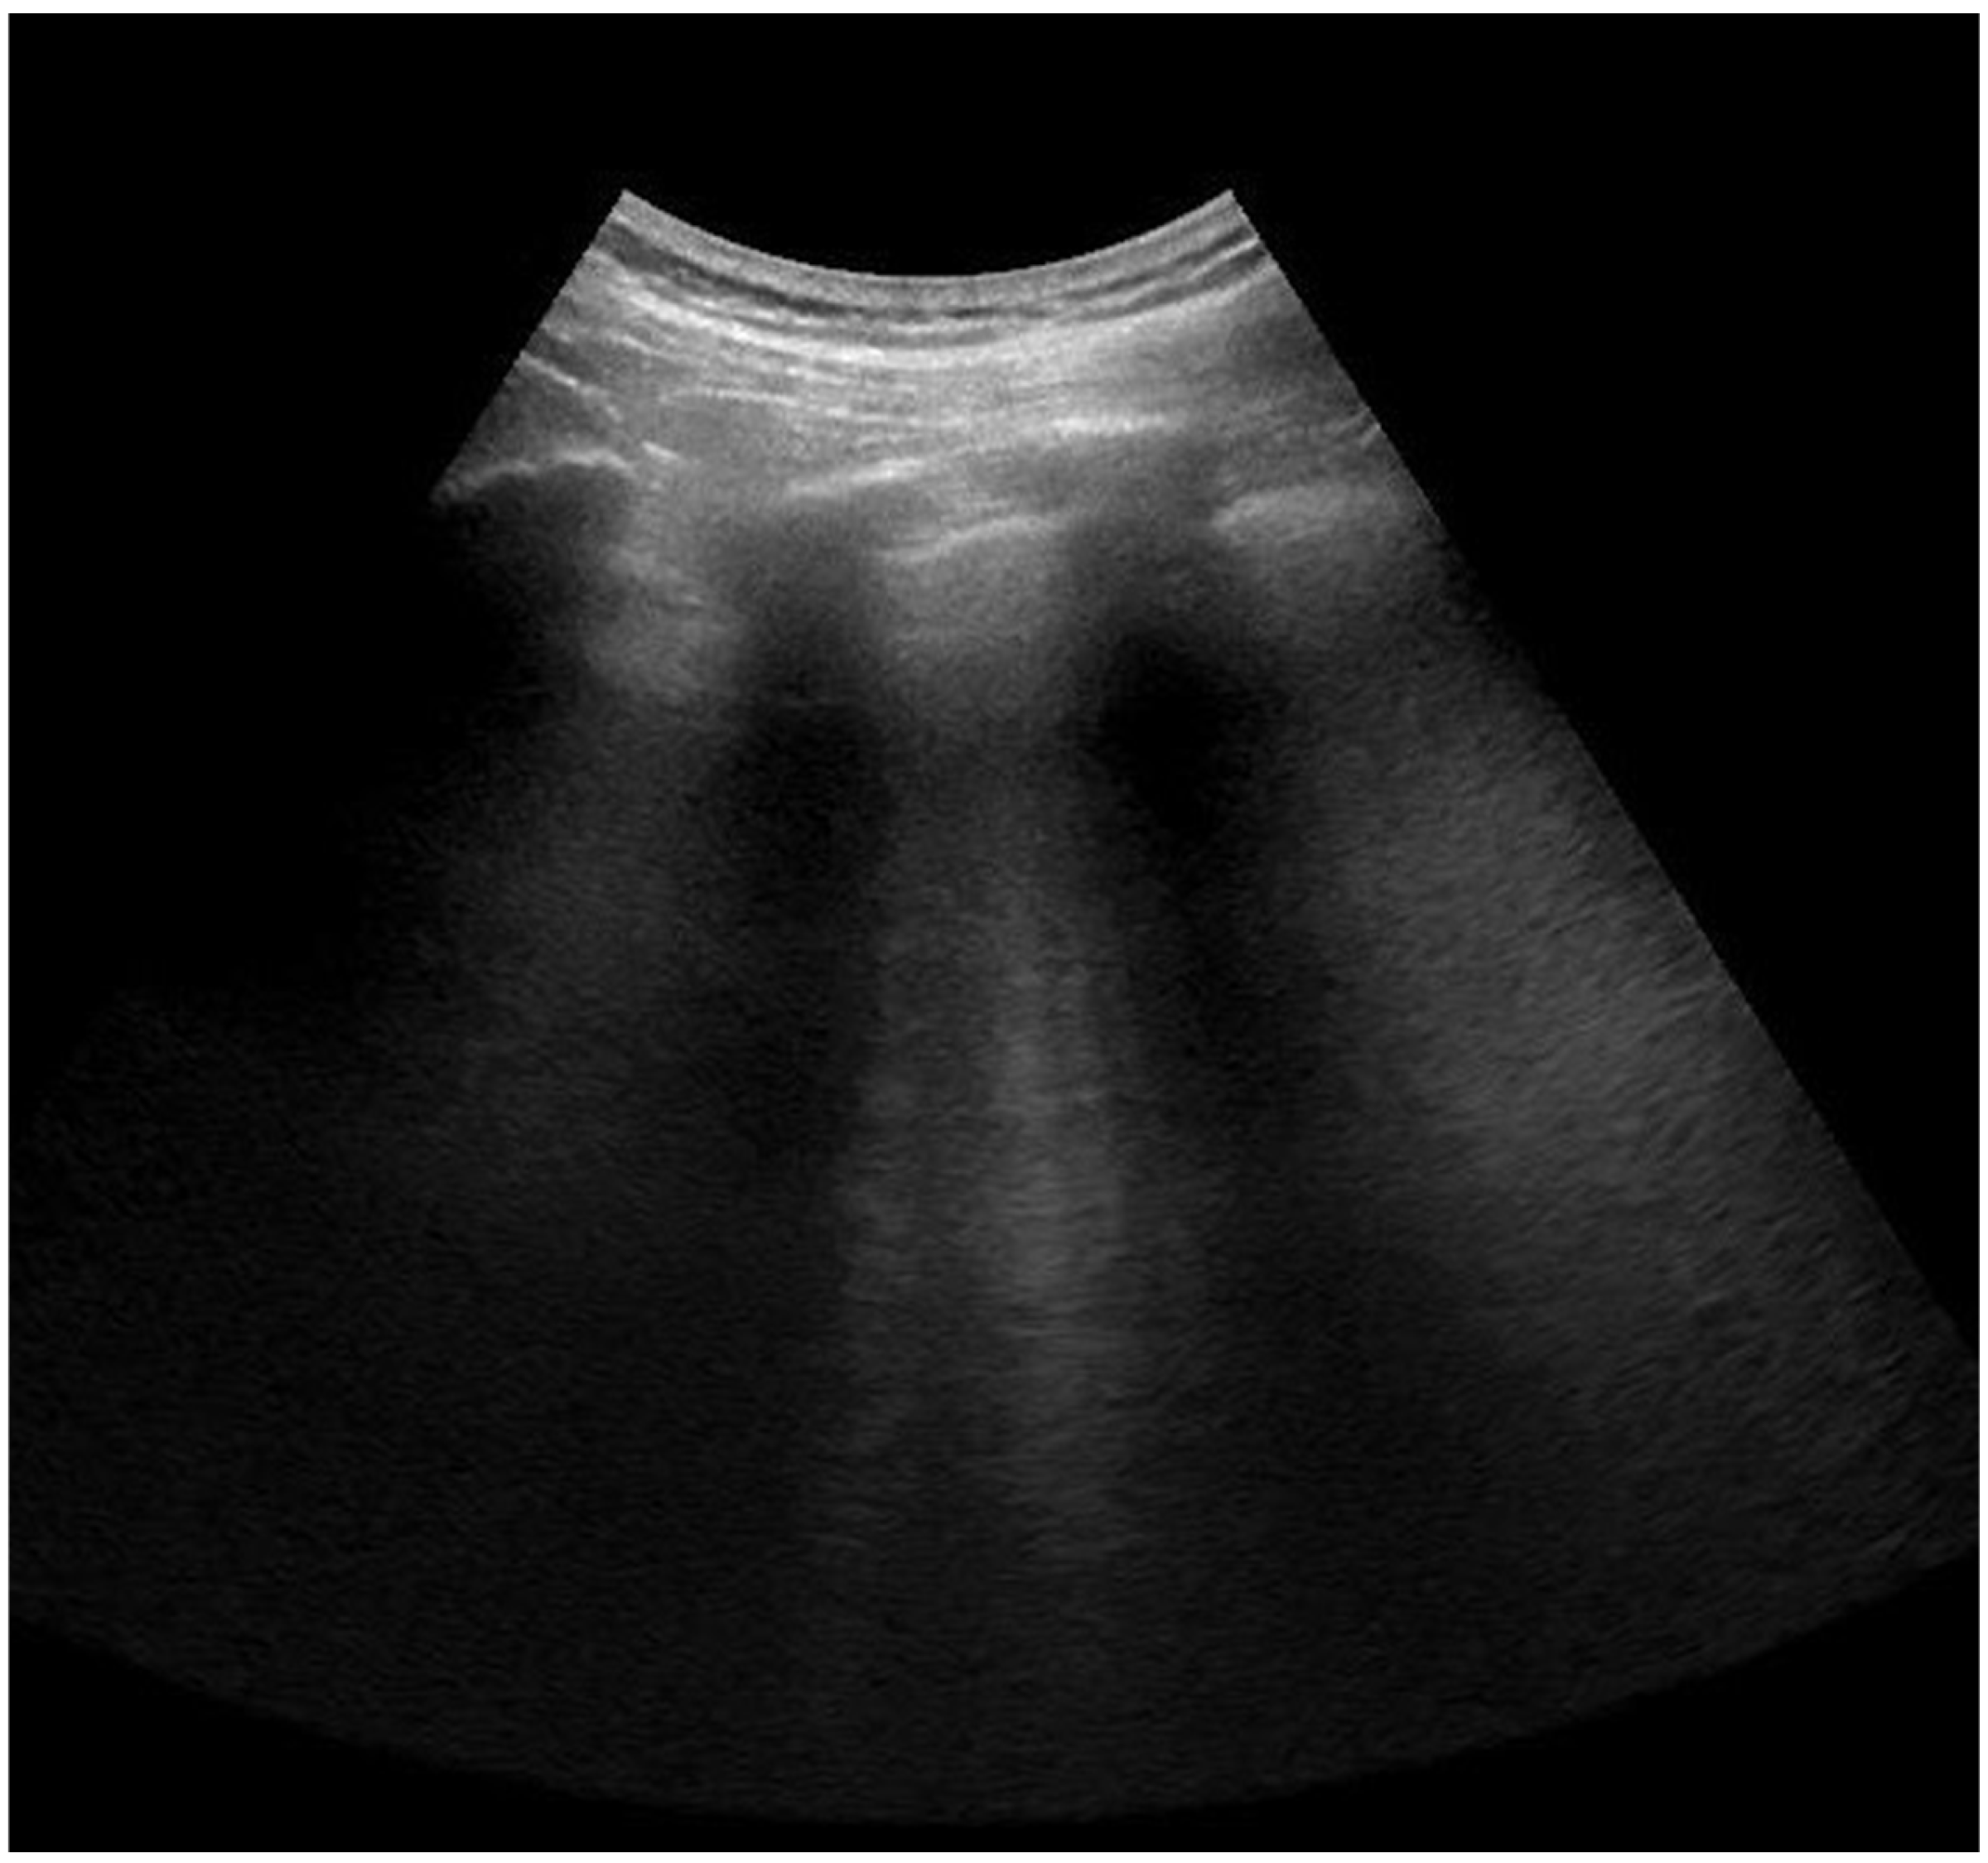

2.4. Lung Ultrasonography and Score Assessment

Appendix A